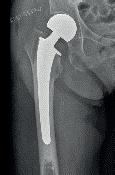

Dislocerede collum femorisfrakturer er den frakturtype af de hoftenære lårbensbrud, der giver de fleste overvejelser ift. implantatvalg. Ældre patienter (typisk 65+ år) har samlet set ca. 35 % risiko for reoperation inden for et år, hvoraf langt hovedparten sker inden for de første tre måneder pga. avaskulær nekrose af caput. Derfor opereres ældre patienter med en hoftealloplastik, hvis de pådrager sig en disloceret collum femorisfraktur. Typen af alloplastik bør være med et cementeret femurstem, som reducerer risikoen for senere reoperation med 50 %. Typisk vil det til de ældre patienter være sufficient med en hemialloplastik, hvor acetabulum lades urørt, da ældre patienters funktionsniveau oftest er så nedsat, at de ikke får acetabular erosion (artrose og smerter) i den forventede kortere restlevetid. Ved meget aktive ældre patienter og hos patienter med forventet lang restlevetid skal man dog overveje en total hoftealloplastik. Hvor aldersgræn-

Efter en hoftealloplastik (hemi og total) for en collum femorisfraktur er der i Danmark ca. 8 % reoperation inden for det

første postoperative år, hvor hovedparten skyldes proteseluksationer. Reoperationsraten er dobbelt så høj som i vores skandinaviske nabolande, hvilket man mener skyldes den kirurgiske adgang, der bruges for at få adgang til hoften. I Danmark bruges oftest posterolateral adgang, mens man i vores skandinaviske nabolande oftest bruger en anterolateral adgang til hofteleddet. En lavere reoperationsprocent kræver et skifte til en anden kirurgisk adgang til hoften eller en forbedring af den adgang, vi bruger nu. De sædvanlige øvrige komplikationer er dyb infektion, acetabular erosion ved hemialloplastik, periprostetisk fraktur, persisterende smerter og benlængdeforskel. Derudover er der forbundet en overdødelighed perioperativt med cementering pga. lungeembolier (Bone Cement Implantation Syndrome).